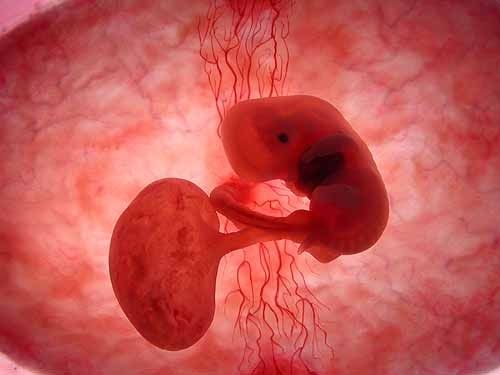

子宫后位

子宫后位